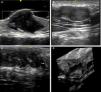

La ecografía cutánea con sondas de alta resolución (20-22MHz) permite la confirmación diagnóstica de los neurofibromas superficiales de manera rápida y no invasiva. Es característica la presencia de zonas hipoecoicas dérmicas de límites bien definidos (neurofibromas cutáneos, localizados en la dermis), dermohipodérmicas irregulares (neurofibromas subcutáneos difusos) o de morfología oval o arrosariada (neurofibromas subcutáneos nodulares) en el tejido celular subcutáneo, siendo el estudio doppler de la vascularización intralesional tenue o ausente50,51 (fig. 11).

Ecografía de alta resolución (20MHz) de distintos neurofibromas. A. Neurofibroma superficial cutáneo donde se aprecia un área hipoecoica bien delimitada en el seno de la dermis que muestra una mínima señal doppler (color rojo). B. Neurofibroma subcutáneo nodular del paciente representado en la figura 9, donde se aprecia una lesión bilobulada bien delimitada heteroecogénica y con leve refuerzo posterior que sigue el trayecto lineal de un nervio periférico laterocervical. C. Neurofibroma subcutáneo que ocupa el tejido celular subcutáneo y la dermis profunda en el que se aprecian zonas difusas (*) y otras cordonales (**).D. Reconstrucción tridimensional ecográfica en la que se aprecia un área lineal convoluta en relación con el engrosamiento de un nervio periférico.